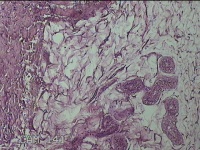

左侧会阴部皮下结节

性别

女

年龄

45岁

临床诊断

皮下结节

一般病史

发现左侧会阴部皮下结节2年余,伴近日局部隐痛不适。

标本名称

大体所见

灰白暗红色结节0.8x0.7x0.3cm一个,表面糜烂。

图3